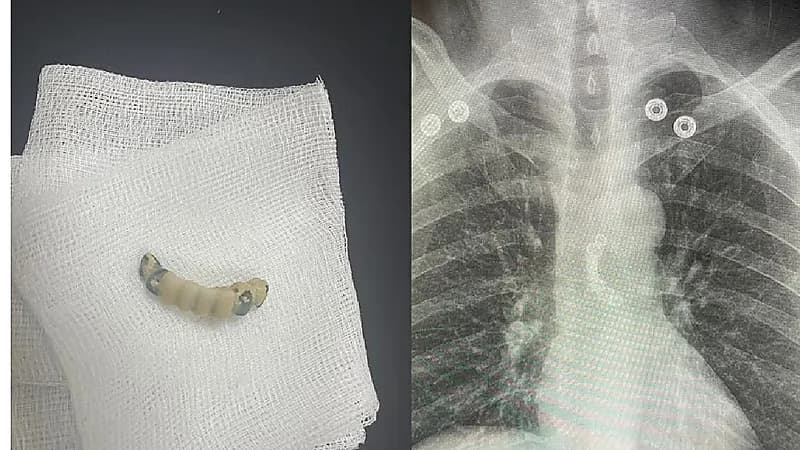

نجحت الفرق الطبية بمدينة الملك سلمان الطبية بالمدينة المنورة في طقم أسنان من منتصف مريء مريض سبعيني ابتلعه بالخطأ.

وحضر المريض إلى قسم الطوارئ بالمستشفى الرئيسي برفقة ذويه بعد أن ابتلع طقم الأسنان الخاص به بالخطأ، وكان يُعاني من آلام شديدة في الصدر وعدم القدرة على البلع، وبعد عمل الأشعة والفحوصات الطبية اللازمة التي أظهرت وجود طقم الأسنان في منتصف المريء.

ونجح الفريق باستخراج الطقم عن طريق عمل منظار الجهاز الهضمي العلوي، وتمت متابعة الحالة حتى استقرارها وغادر المستشفى بصحة جيدة .